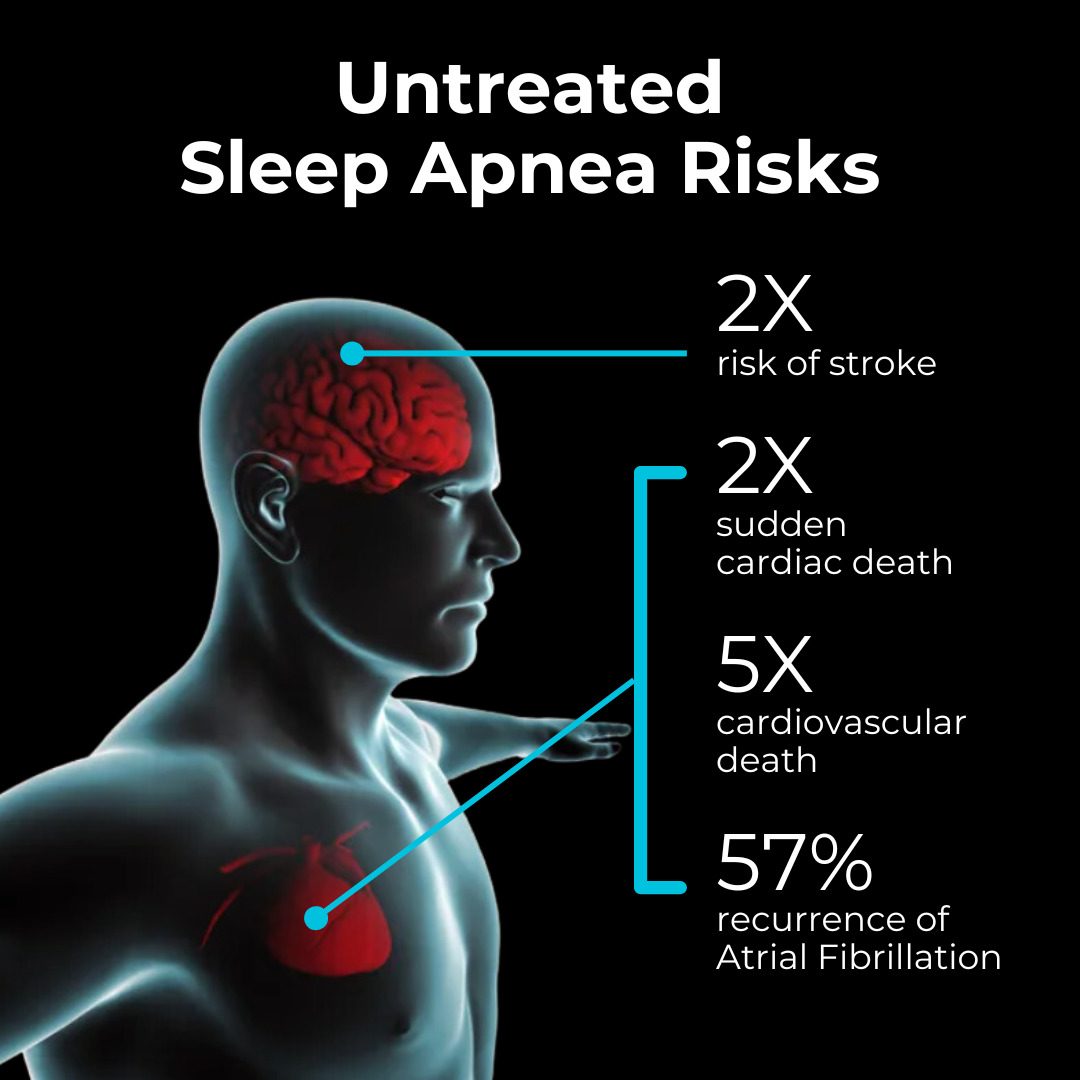

THE LINK BETWEEN STROKE AND SLEEP APNEA

THE LINK BETWEEN STROKE AND SLEEP APNEA november-2024-dsm-newsletter